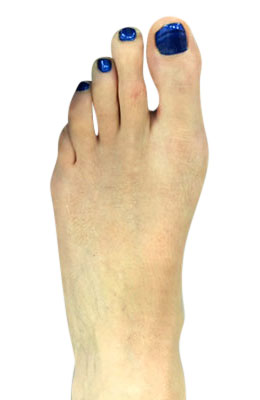

Before

Minimally Invasive Bunion Surgery featuring the CrossRoads miniBunion™ System before

After

Minimally Invasive Bunion Surgery featuring the CrossRoads miniBunion™ System after

Minimally Invasive Bunion Surgery featuring the CrossRoads miniBunion™ System

Eva is a 24-year-old female who had just began working at a job that required high fashion shoes. She was in constant pain but could not take time off work. Our miniBunion™ Minimally Invasive Bunionectomy allowed her to continue to work and be on her foot with full recovery and return to regular shoes by 6 weeks. She had an amazing range of motion, no more bunion pain, and absolutely no visible incision. After picture taken six weeks post-surgery.